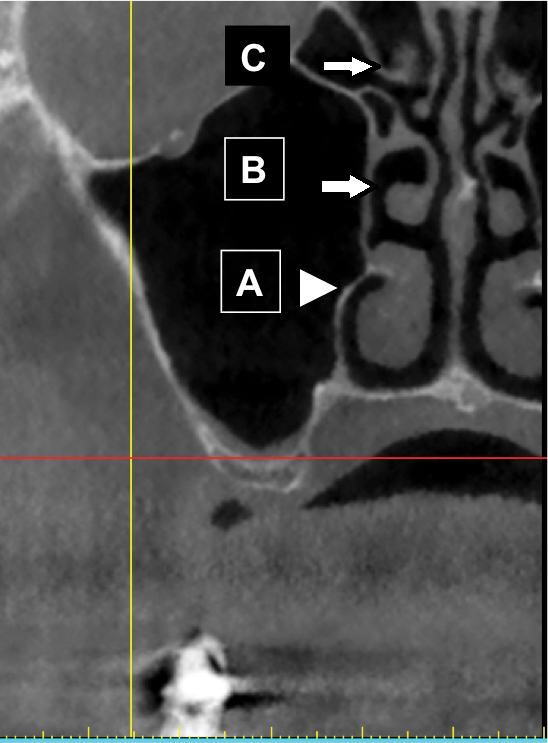

Concha, or Turbinates

In the nose, there is an inferior, middle, and superior turbinate (Figure 24). These structures are also called concha. The inferior turbinate is an independent facial bone, whereas the middle and superior turbinates are part of the ethmoid bone. When the mucosa around a turbinate is inflamed, the turbinate appears distended.

Fig 24. Turbinate bones: cross-sectional view. They are found within the nose. There is an inferior (A), middle (B), and superior turbinate (C).